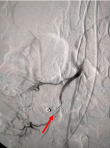

Follow-up and outcome of intervention: on the fifth day of treatment, the patient experienced a severe complication in the form of massive hematochezia, prompting an urgent interventional response. A subsequent angiography procedure was performed, which identified the source of the hemorrhage as a pseudoaneurysm of the biceco-appendicular artery, a branch of the superior mesenteric artery (Figure 1); this life-threatening lesion was then successfully treated via endovascular embolization using four Vortex 0.18 coils, each with a diameter of 3mm (Figure 2).

Figure 2: post-embolization control angiogram showing successful occlusion of the pseudoaneurysm with coils and maintained patency of the parent artery